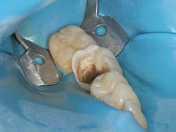

Füllungstherapie  |  Amalgamsanierung unter Kofferdam

Kofferdam – vor, während und nach der Behandlung

Füllungen und Aufbaufüllungen unter Kofferdam

Lange Zeit war die Amalgamfüllung im Seitenzahngebiet das Füllungsmaterial der Wahl, da keine auf Dauer haltbaren Materialien zur Verfügung standen. Mit der Entwicklung der Komposite als Füllungen und Aufbaufüllungen zur Vorbereitung stark zerstörter Zähne für Überkronungen ergaben sich neue Möglichkeiten in der Füllungstherapie. Voraussetzung für den dauerhaften Halt der Komposite ist eine absolute Trockenlegung des Arbeitsfeldes, um frei von Atemluft und Speichel die Verbindung zwischen Füllungsmaterial und Zahn zu gewährleisten.

Dies wird durch das Anlegen des Kofferdams erreicht. Das Bild zum Kofferdam mag etwas unheimlich anmuten, aber die Patienten empfinden es eher als angenehm und entspannend.

Vorteile des Kofferdam

• Behandlung findet scheinbar außerhalb des Mundes statt

• freies Atmen und Schlucken jederzeit möglich

• keine Abwehrreaktionen gegen Instrumente, kein Würgereiz

• Schutz für Zunge und andere Weichteile

• reduzierte Wahrnehmung schlecht schmeckender Wirkstoffe

• Erleichterung des langen Mundöffnens durch Spannung des Gummis

PKR – Plastisch-keramische Restaurationen

Plastisch keramische Restaurationen bestehen zu 85 Prozent aus kleinsten Keramik-, Glas- und Quarzpartikeln, während der eigentliche Kunststoffanteil nur noch 15 Prozent ausmacht. Es handelt sich dabei eher um formbar gemachte Keramik als um Kunststoff.

Diese Rekonstruktionen werden in der sogenannten „Adhäsivtechnik” mit dem Schmelz oder Dentin verklebt und mit Licht gehärtet. Neue Hybridcomposite mit einem erhöhten Füllkörpergehalt eignen sich auch für den Backenzahnbereich, also auch dort, wo Kaudruck entsteht.

Bei der plastisch keramischen Restauration ist ein hoher Aufwand nötig, um komplette Kauflächen anatomisch und funktionell wieder aufzubauen.